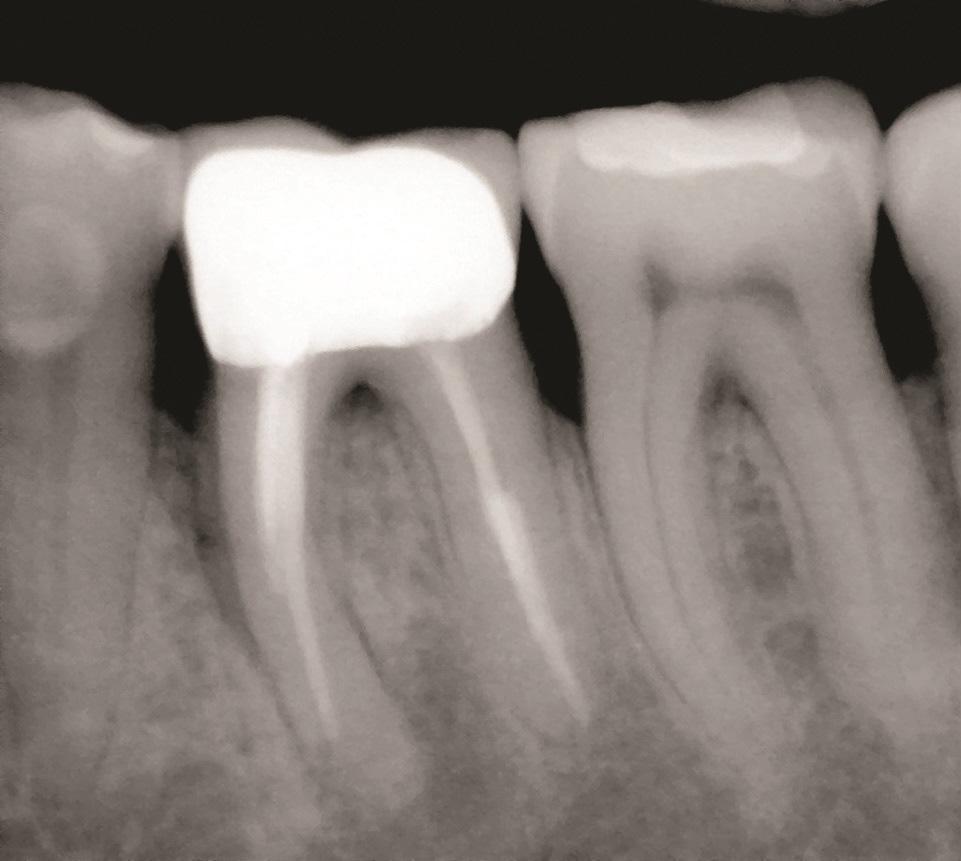

К таким патологическим состояниям относятся вертикальные переломы корней, перфорации корней, пародонтит с поражением корней из-за проблем в области фуркации или сближения корней, сочетанные эндодонтическо-пародонтальные дефекты на фоне коротких корней, устойчивые фуркационные дефекты, значительные не поддающиеся лечению внешние резорбтивные дефекты и другие (Фото 1–4). Когда подобные состояния затрагивают однокорневые зубы, удаление часто является единственным способом устранения патологии. Однако в случае многокорневых зубов существует дополнительная возможность: полное удаление источника патологии с одновременным сохранением функциональности зуба, что демонстрирует опубликованные показатели выживаемости на уровне 80–90%. При правильном выполнении с учетом описанных в статье факторов такое функциональное состояние может сохраняться в долгосрочной перспективе со средним сроком службы от 6 до 20 лет.

Фото 3: Зуб 3.6 с латеральной и апикальной потерей кости в области переломанного мезиального корня.